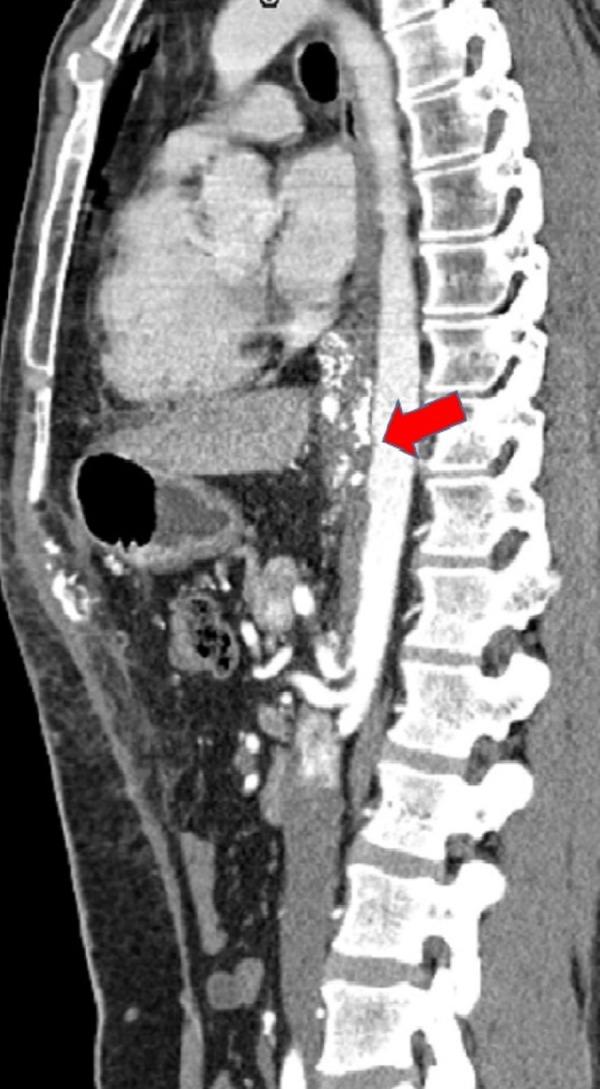

Disease assessment based on measurements of size and anatomic involvement have historically been central to surgical strategy. We propose this to be an outdated concept, which should be replaced by a deeper understanding of tumor biology and careful treatment planning. Report of case: A 34-year-old male was diagnosed with a Siewert Type 3 locally advanced cancer of the gastroesophageal junction, involving the coeliac axis and the superior mesenteric artery (SMA). He was treated with neoadjuvant chemotherapy, followed by chemoradiation, and then proceeded to surgery, at which time the tumor was judged unresectable. After extensive planning, a further surgery was attempted - an extended gastrectomy with distal esophagectomy, left hepatectomy, and splenectomy were performed. Additionally, the coeliac axis and the SMA were excised, followed by reconstruction of the hepatic artery and the SMA with grafts. Adjuvant chemotherapy was administered, and the patient is recurrence-free after five years follow-up.